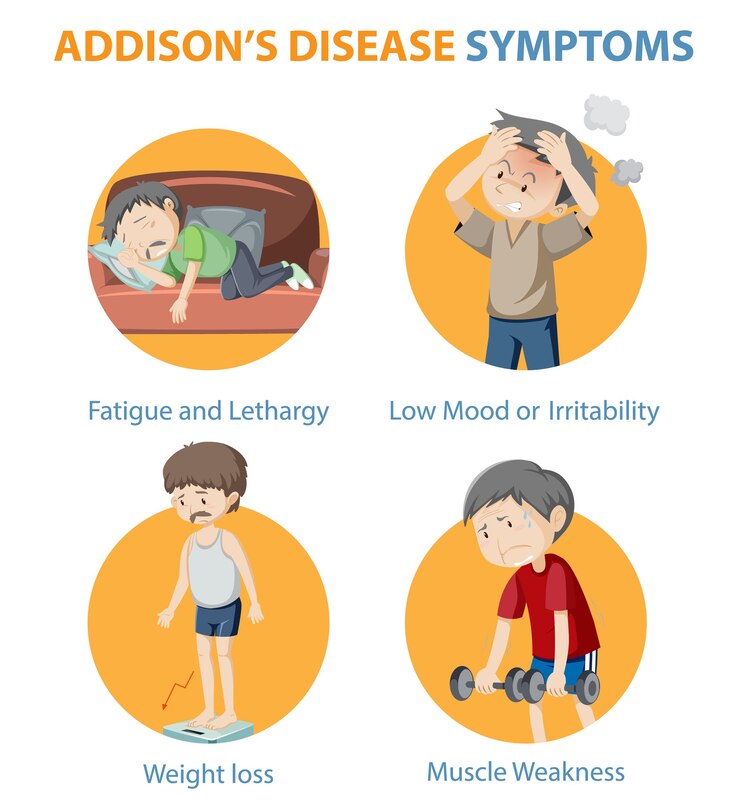

علائم بیماری آدیسون میتواند از فردی به فرد دیگر متفاوت باشد. علائم معمولاً در طول زمان به کندی ایجاد میشوند و معمولاً مبهم و در بسیاری از شرایط (غیر اختصاصی) مشترک هستند. این اغلب منجر به تاخیر در تشخیص صحیح بیماری آدیسون میشود. در موارد نادر، علائم بیماری آدیسون میتواند به سرعت ایجاد شود و باعث ایجاد وضعیتی به نام نارسایی حاد آدرنال شود.

خستگی شایع ترین علامت بیماری آدیسون است. یکی دیگر از علائم اولیه رایج بیماری آدیسون ایجاد لکههای پوستی تیره تر از پوست اطراف است (هیپرپیگمانتاسیون). این تغییر رنگ بیشتر در نزدیکی اسکارها، توسط چینهای پوستی مانند بند انگشتان و روی غشاهای مخاطی مانند لثهها اتفاق میافتد. ناهنجاریهای پوستی میتوانند ماهها یا سالها قبل از بروز علائم دیگر باشند اما در هر فردی رخ نمیدهد.

انواع مختلفی از علائم گوارشی از جمله تهوع، استفراغ و درد شکم ممکن است وجود داشته باشد. اسهال کمتر شایع است اما ممکن است رخ دهد. افراد مبتلا ممکن است اشتهای ضعیف و کاهش وزن ناخواسته داشته باشند و ممکن است دچار خستگی پیشرونده و ضعف عضلانی شوند. درد عضلانی (میالژی یا myalgia)، اسپاسم عضلانی و درد مفاصل نیز ممکن است رخ دهد. کم آبی همچنین میتواند بر افراد مبتلا به بیماری آدیسون تأثیر بگذارد.

یک علامت اضافی که ممکن است رخ دهد فشار خون پایین (افت فشار خون یا hypotension) است که میتواند باعث سبکی سر یا سرگیجه در هنگام ایستادن شود. از دست دادن موقت هوشیاری (سنکوپ یا syncope) در برخی موارد ممکن است رخ دهد. بیماری آدیسون همچنین میتواند منجر به تغییراتی در احساسات و رفتار شود. این اختلال با تحریک پذیری، افسردگی و تمرکز ضعیف همراه است.